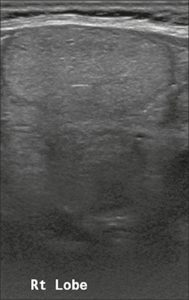

Hình 19. Hình ảnh nhân giáp dạng đặc (2 điểm), giảm âm rất mạnh (3 điểm), rộng hơn cao (0 điểm), có bờ trơn láng (0 điểm), và không có các ổ tăng âm hay bóng lưng (0 điểm). Do đó, tổng điểm là 5 điểm và mức độ nguy cơ được phân loại là TR4.